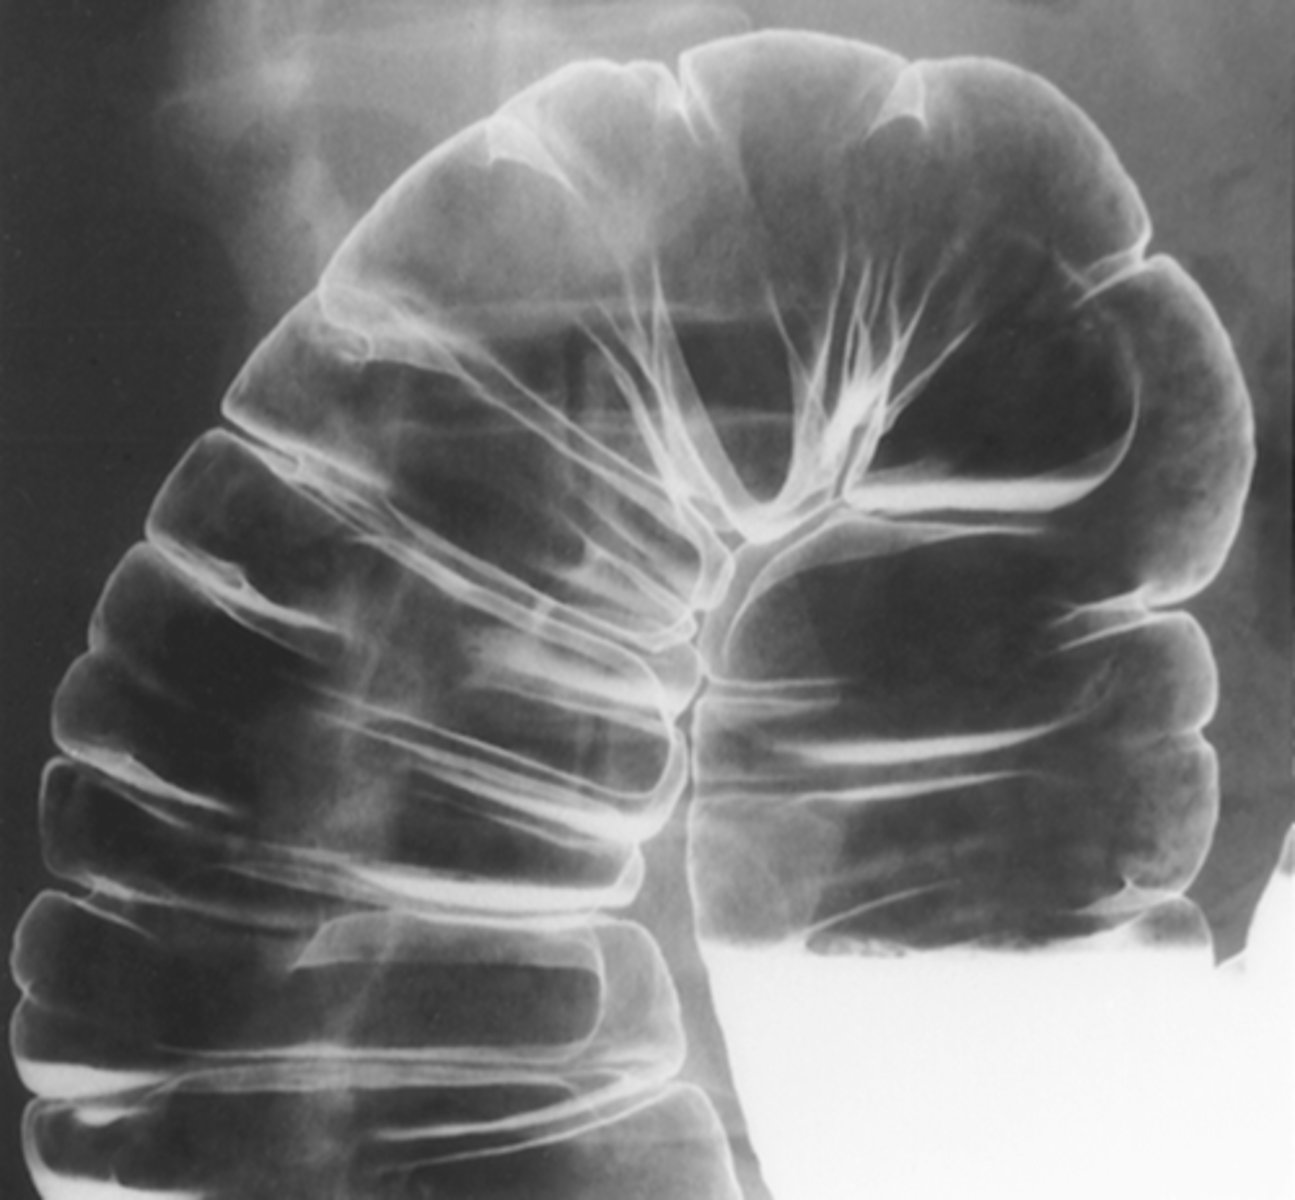

Ulcerative colitis

apple core lesion- colon CA

diverticulosis